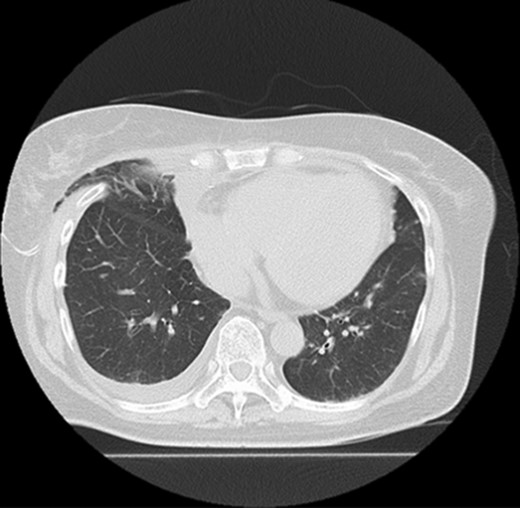

Five days after surgery, she complained of right chest wall pain and discomfort on inspiration. Computed tomography (CT) revealed that part of the right upper lobe of the lung had herniated through the right fourth intercostal space (Fig. 1). Lung hernia was diagnosed. The herniated lung was manually repositioned by compression bandages (Fig. 2). On postoperative Day 11, 6 days after recognition of the herniation, the lung hernia was not apparent on CT. The patient was discharged home without symptoms on postoperative Day 12.